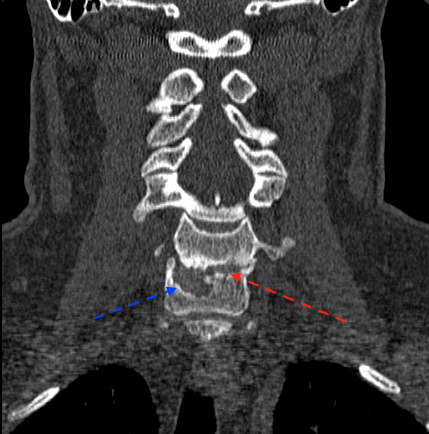

A continuación, presento imágenes de un caso con pseudoartrosis C6-C7 intervenido en otro centro en 1995, sin informes quirúrgicos del material de implantación. La flecha azul señala la ubicación lateral derecha de la(s) caja(s) con extrusión anterior parcial del material. La flecha roja delimita la altura preoperatoria del disco; parece que existe cierta integridad de platillos en la hemivértebra izquierda.

El paciente presentaba una clínica de dolor de características mecánicas y ubicación similar a preoperatorio. La braquialgia izquierda no se había resuelto tras la cirugía. Se planificó la cirugía para retirar la(s) caja(s), descomprimir y fusionar por vía anterior. La fusión dependería de la integridad y volumen residual de los platillos para realizar una intersomática o corpectomías + reconstrucción.